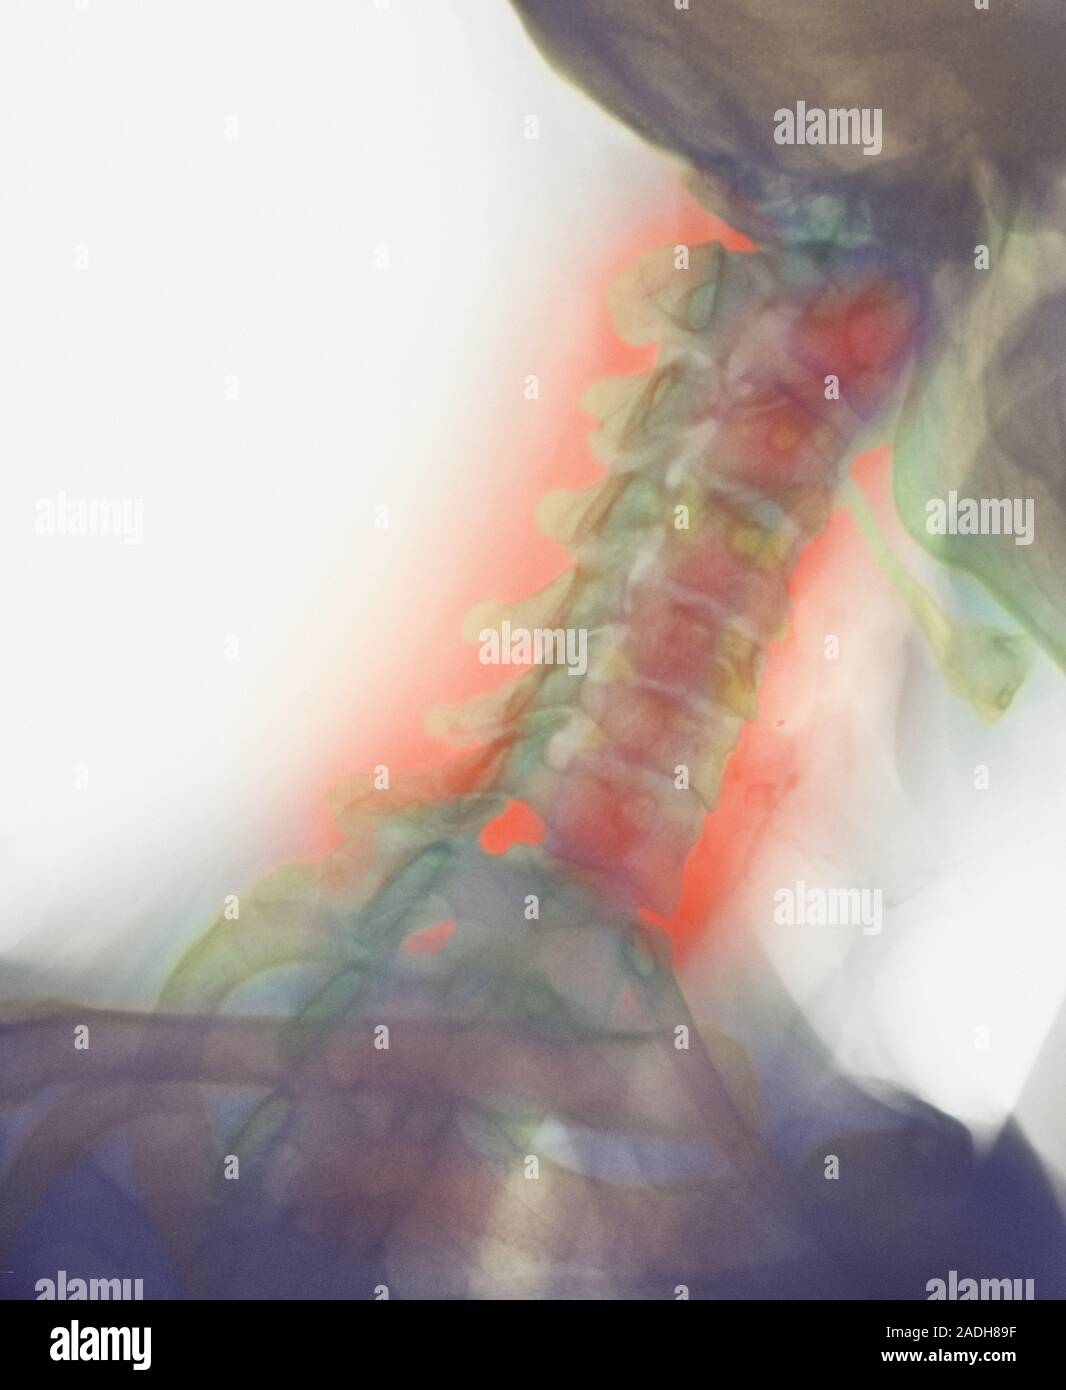

From www.alamy.com

Osteoarthritis of the cervical spine. Coloured lateral Xray of the Osteoarthritis In Neck And Head Healthcare providers sometimes call it osteoarthritis of the neck or arthritis of the neck. cervical spondylosis (also called cervical osteoarthritis) is a condition involving changes to the bones, disks, and. osteoarthritis in the neck is the degeneration of joints, vertebrae, and discs in the cervical portion of the spine. Oa can affect all joints, including our knees, hands,. Osteoarthritis In Neck And Head.